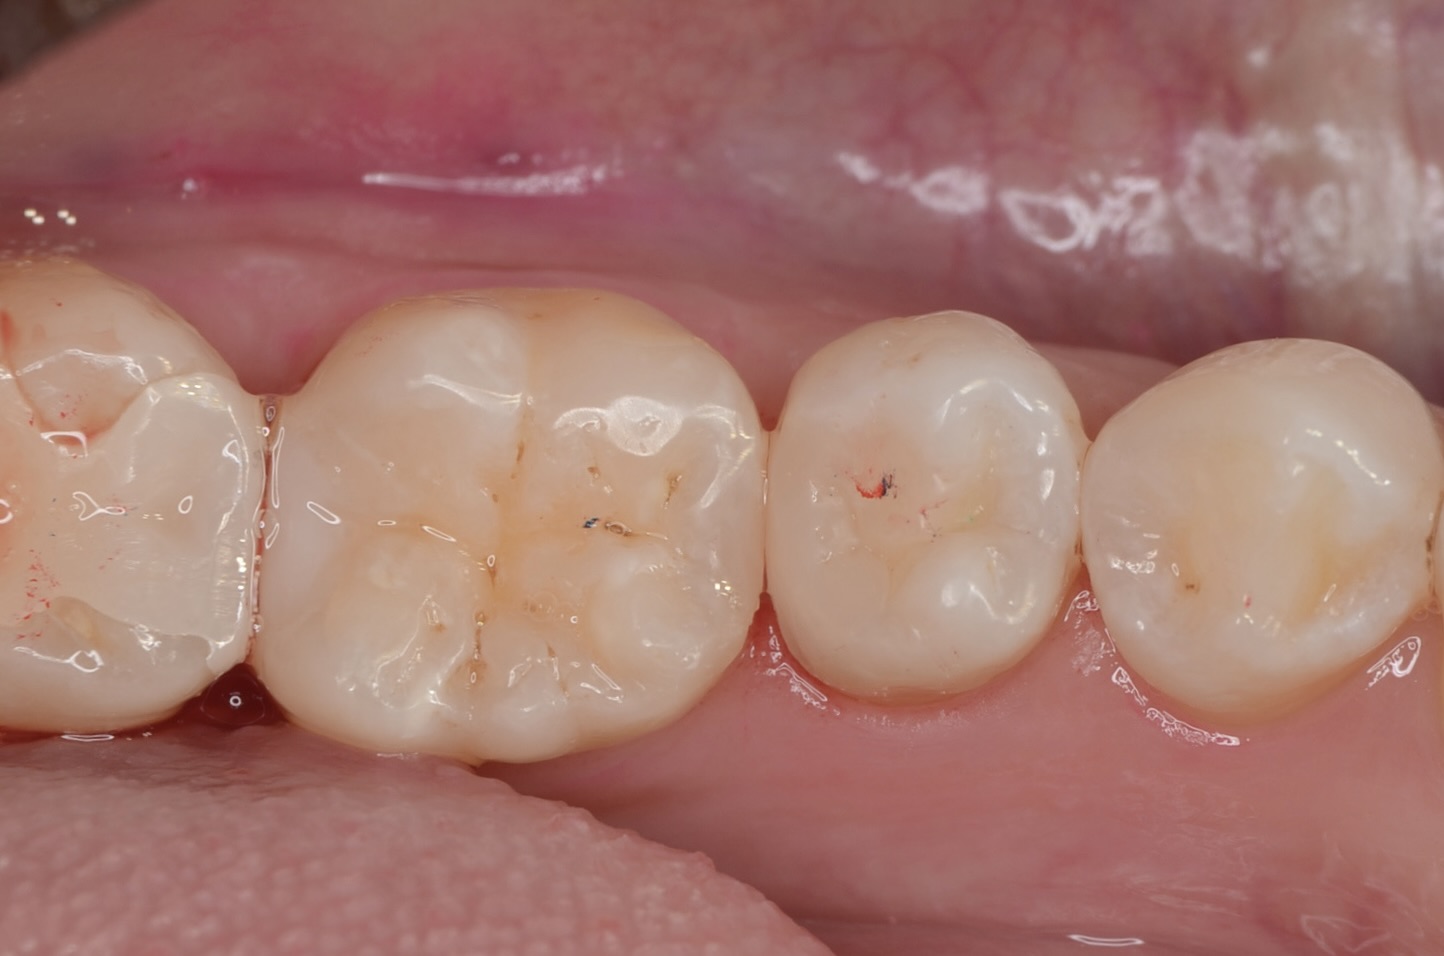

後日

今度は6番の遠心面を治療します。 -

虫歯除去

完全に虫歯を取り除きました。 -

ダイレクトボンディング

天然歯の自然な形態を模倣してレジンを充填しました。 -

後日、形態修正

研磨をしっかり丁寧にすることで、レジンと歯質の段差を修正し、虫歯になりにくくします。 -